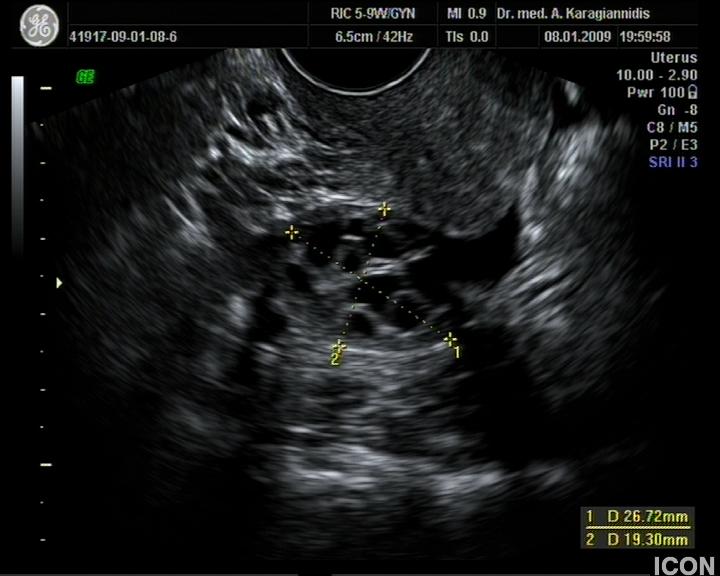

Ενδοκολπικός U/S έσω Γεννητικών Οργάνων